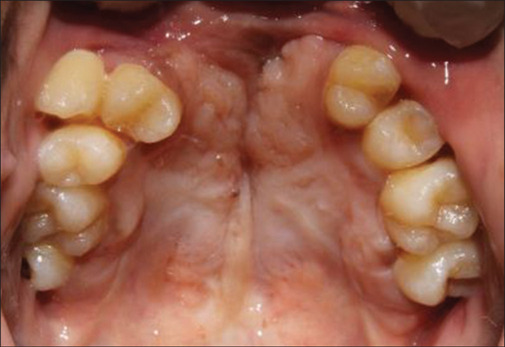

唇腭裂是影响个人生活质量的最常见口面畸形。由于前颌骨缺失,双侧唇腭裂最难治疗,在这种情况下,可摘义齿是唯一能满足美学、功能和语音要求的治疗方法。在本病例报告中,我们讨论了一种新颖的技术,即用固定的空心假体修复双侧腭裂患者,这种假体可以替代缺失的软硬组织,但重量很轻。这种独特的假体解决方案可以为看似受损的情况设定新的治疗标准。

Cleft lip and palate are the most common orofacial anomalies affecting the quality of life of an individual. Bilateral cleft lip and palate are the most difficult to treat due to missing premaxilla, and removable prosthesis is the only treatment in such situations to satisfy esthetics, function, and phonetics. In this case report, we have discussed a novel technique of rehabilitating a bilateral cleft palate patient with a fixed hollow prosthesis that would replace the missing hard and soft tissue, yet is light weighed. This unique prosthetic solution could set a new standard of treatment in a seemingly compromised situation.